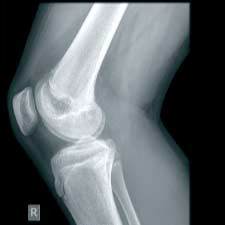

Immagini di alta qualità. Bassi dosaggi. Flusso di lavoro efficiente. DX-G: un livello a parte.